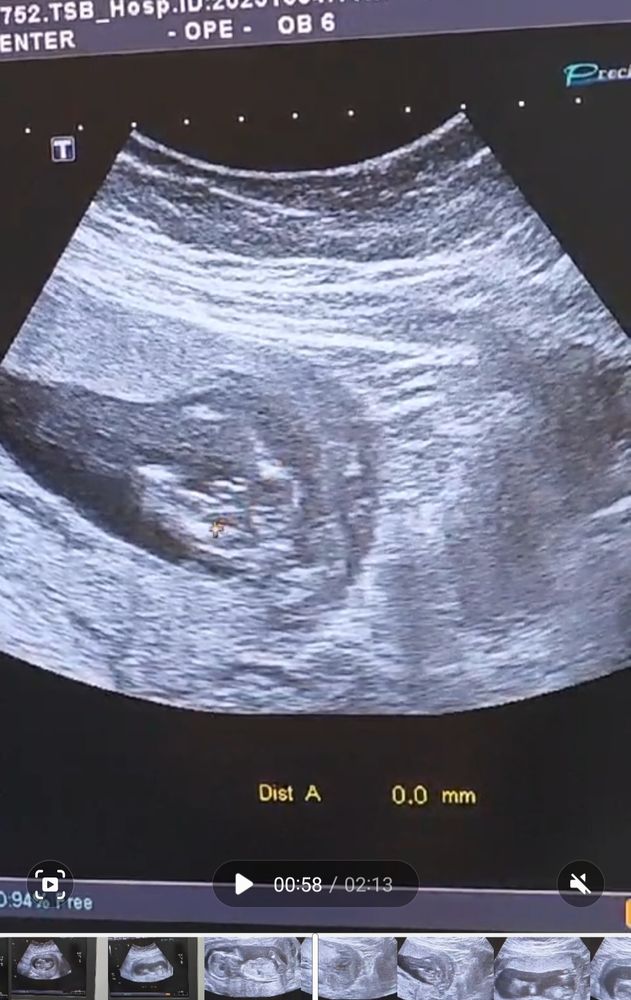

Так выглядит мой мальчик😁

Сын! У нас будет сын !! Пол малыша на 1 скрининге